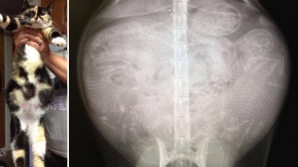

Taguri: GALERIE FOTO Creativitatea unora nu cunoaşte limite! Invenţii care te vor lăsa mască (IMAGINI INCREDIBILE) IMAGINI SPECTACULOASE cu Super Luna albastră sângerie, surprinse pe cerul de la Chişinău (GALERIE FOTO) Lucrările de deblocare a drumurilor din ţară, în plin proces. La Criuleni, troienele trec de un metru înălţime (FOTO) Phenianul a publicat imagini din timpul ultimului test balistic (GALERIE FOTO) GALERIE FOTO. Cum arată noua casă de vacanţă a preşedintelui de la Kremlin Cum arată scena de la Kiev care va găzdui marele concurs de muzică Eurovision 2017 (GALERIE FOTO) INCREDIBIL: Cum ar fi arătat Michael Jackson la 50 de ani, dacă nu îşi făcea nicio operaţie estetică (FOTO) IMPRESIONANT: Cum arată sarcina la diverse specii de animale (FOTOGRAFII ROENTGEN) Cele mai înfricoşătoare mâncăruri pentru Halloween. Ai încerca aşa ceva (FOTO) Ei au topit milioane de inimi femeieşti: Topul celor mai atrăgători bărbaţi din lume (FOTO) Vezi cât de mult se schimbă aspectul fizic al persoanelor pe parcursul zile (FOTO) QUIZ: Şi-a deghizat fiica în diverse costume în timp ce dormea. Recunoşti toate personajele? (FOTO) Peisaje rupte din basme: Colecția celor mai frumoase fotografii din 2016 surprinse în natură AMUZANT: Sunt persoane reale însă seamănă leit cu eroii desenelor animate (GALERIE FOTO) Când imaginația tatălui fotograf ajunge prea departe! Cele mai terifiante poze de familie (FOTO) Adevărata faţă a drogurilor. Cum se schimbă fizic persoanele care consumă substanțe interzise (FOTO) Vei RÂDE CU LACRIMI! Cele mai penibile momente de la nunți, surprinse în poze VIRAL pe Internet! Rușii dau din nou lovitura cu o metodă inedită de reparație a drumurilor (FOTO) Galerie FOTO. Cum arăta clubul Colectiv după incendiu Atunci și acum! Schimbările DRAMATICE suferite de Pământ în câțiva ani (GALERIE FOTO) NU E PHOTOSHOP! Cum arată Pământul, fotografiat din spațiu (GALERIE FOTO) AMUZANT şi VIRAL pe Internet! FOTOREPORT cu cei mai ghinionişti oameni din lume BOMBE ecologice în mijlocul oraşelor. Cum arată cimitirele de maşini abandonate în China (FOTO) Germanii vor să detroneze cu acest model legendarul Volkswagen Golf (GALERIE FOTO) Galerie FOTO cu cele mai importante premiere mondiale ale Salonului Auto New York 2015 Premierele Salonului Auto de la Detroit în mai puţin de 180 de secunde (VIDEO) Peisaje de iarnă inedite. Cum arată Moldova în luna lui gerar (GALERIE FOTO) Bate vântul prin Chișinău! Cât de pustii au fost străzile capitalei de Crăciun pe stil vechi (FOTO) Feerie pe străzile capitalei. Cum arată Chişinăul nocturn în ajunul sărbătorilor de iarnă (GALERIE FOTO) GALERIE FOTO impresionantă de la meciul dintre Moldova şi Liechtenstein 1 ABCDEFGHIJKLMNOPQRSTUVWXYZ IMPORTANTE ALTELE